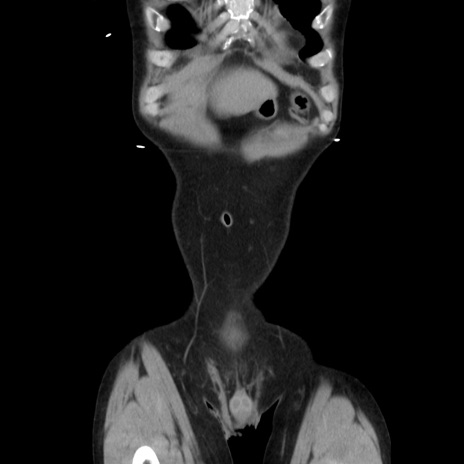

症例37(冠状断像)

【症例】40歳代 男性

【主訴】腹痛

【現病歴】4時間ほど前に電車に乗車中に臍部上より腹痛出現。徐々に増悪し起立困難となり、救急外来受診。生ものは数日食べていない。今朝お雑煮を食べた。

【身体所見】BT 36.8℃、BP 117/84mmHg、HR 91/min、SpO2 97%、苦悶様、腹部:臍上部広範囲圧痛あり、反跳痛±

【データ】WBC 8100、CRP 0.03